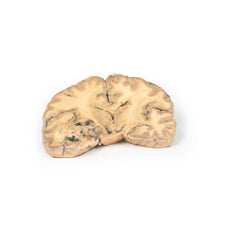

3D Printed Metastatic Carcinoma in the Brain

Pathology

The specimen is the cerebrum sliced horizontally. On the superior view, the right hemisphere is

clearly enlarged, particularly in the parietal region where the gyrae are widened and 3 cystic tumours are

evident. The largest, 5 cm in diameter, is in the right parietal region. A smaller tumour, 2 x 1.5 cm in

diameter, is seen close to the posterior margin of the largest tumour. A third one, 1.5 cm in diameter, is

present in the left parietal region. The tumours have mainly involved white matter. The wall of each lesion is

composed of shaggy friable greyish tissue. At necropsy, there was ulceration of the largest tumour into the

right lateral ventricle (seen more clearly when the inferior surface is examined). Sub-falcine herniation was

also seen, as is displacement of the basal ganglia and internal capsule. Histological examination revealed

metastatic carcinoma in the viable areas. Other metastases were found in the liver and bone. Histology of a

liver metastasis was consistent with origin from a primary carcinoma of breast.